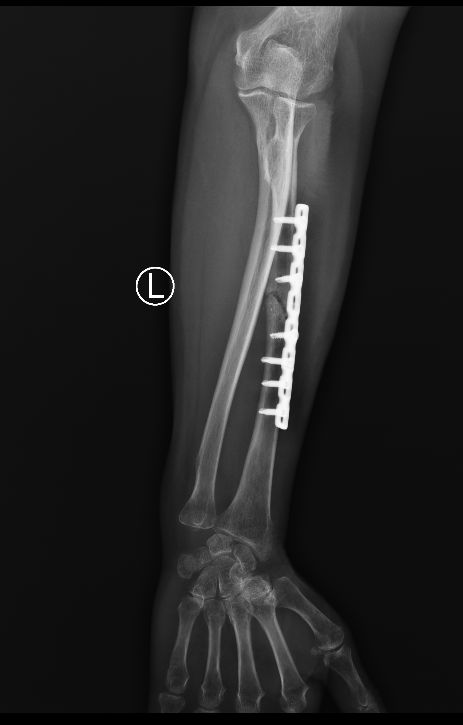

很多患者在复查X片时看到骨折处依旧“黑乎乎一片”,心里立马咯噔一下:“一个月了,怎么还没长骨痂?是不是不愈合了?”这种焦虑非常普遍。从患者角度来说,等待骨痂显影的过程,本身就像是一场煎熬,每天盯着患肢,生怕出现什么“失败的信号”。

答案并不绝对。临床上,大部分长得快的骨折,比如儿童,往往两三周就能看到毛糙的影子,而成年人通常需要四到六周才能显影。骨头不是流水线,愈合速度受很多因素影响,年龄、骨折部位、骨折类型、血供情况、营养和固定方式,都能左右进度。有些髋部或胫骨远端的骨折,血液循环差,骨痂本来就起步慢。

如果影像上完全没动静,我们会警惕以下几种情况:一是固定不牢,骨折端微动过多,骨痂还没来得及长就被“搅掉”;二是局部血供差,比如开放性骨折或软组织损伤严重,导致“养分运不过去”;三是全身因素,包括营养不足、长期抽烟喝酒、内分泌紊乱,甚至合并糖尿病等。还有一种常被忽略的情况,就是药物影响,比如长期吃糖皮质激素,也可能让骨痂迟迟不长。

在临床上,一个月没有骨痂,并不等于骨头一定不愈合。多数情况下,医生会建议再观察2-3周,并同时检查患者的全身情况。影像学上没有骨痂,不代表显微层面没动静,有时骨折周围已经有纤维性连接,只是X片暂时看不清楚。如果确实怀疑愈合迟缓,医生可能会调整固定方式,增加支撑,或者考虑促进骨痂形成的治疗,比如低强度脉冲超声、磁场刺激等。部分患者会被建议增加蛋白质和钙磷摄入,当然,补钙不是万能的,关键还是整体代谢环境。